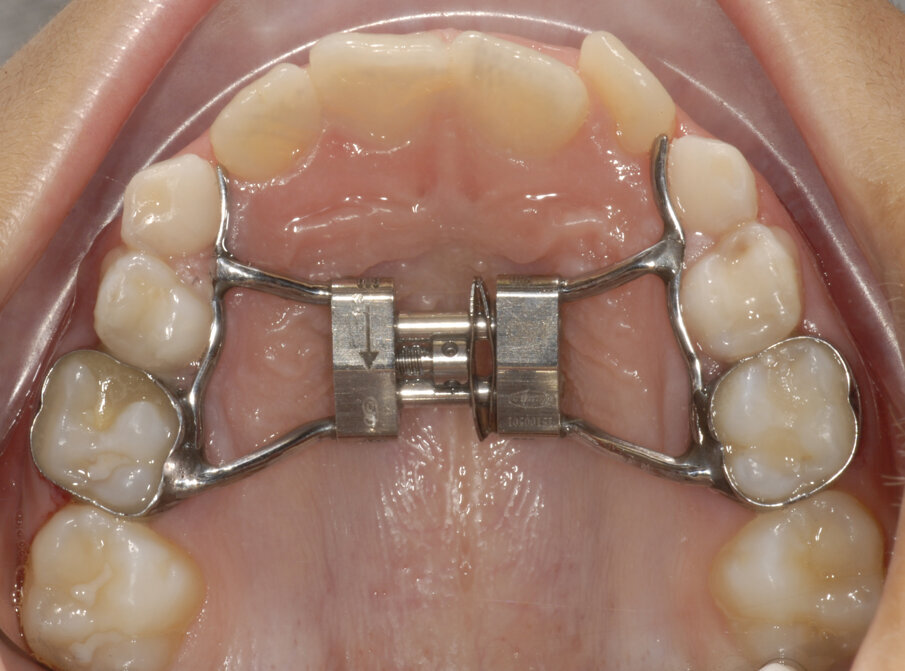

Alessandro, 8 anni, viene sottoposto ad una CBCT (Figg. 21, 22) dopo una valutazione iniziale dove si è riscontrato un percorso di permuta difficile dei canini permanenti (1.3-2.3).

Tramite scansione digitale delle arcate vengono ottenuti dei modelli virtuali, i file .STL vengono inviati al laboratorio ortodontico per la realizzazione di un espansore lento del palato Leaf Expander® (Leone, Sesto Fiorentino (FI), Italia).

Il dispositivo customizzato e prodotto tramite laser sinterizzazione (Fig. 23), viene cementato su “E” e riattivato periodicamente. Dopo la fase di espansione e stabilizzazione (Fig. 24), vengono ottenuti dei nuovi modelli virtuali per la progettazione (Fig. 25) e produzione (Fig. 26) tramite fresatura di una barra di Nance in Trilor® (Bioloren, Seregno, Italia). Alessandro, una volta cementata la barra di Nance (Fig. 27), viene sottoposto ad estrazione anticipata dei canini (5.3-6.3) e dei primi molari decidui (5.4-6.4).

Fig. 21_CBCT mascellare superiore.

Fig. 22_Dettaglio del percorso di eruzione dei canini.

Fig. 23_Cementazione Leaf expander full digital.